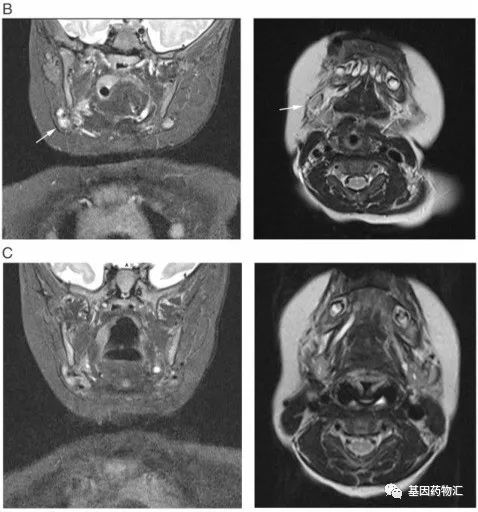

用药前的MRI检测提示,Tony右侧颈部的肿瘤体积达到了5.5×4.5×4.4厘米。后续,Tony开始接受口服拉罗替尼治疗。

这些喜人的改变每天都在发生。至第56天复查MRI时,Tony几乎所有转移病灶都小时了,只剩下一个1.2×1.2×0.8厘米大小的右侧淋巴结病灶。就连这个病灶,在第二次复查MRI的日子,也完全消失了!